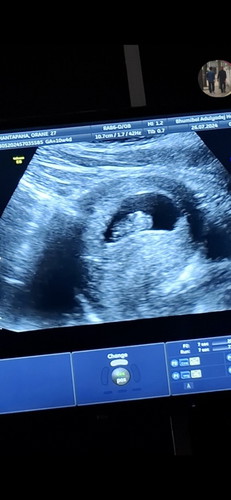

นับตามอายุครรภ์ที่ ปจด.มาครั้งสุดท้าย ตอนนี้ได้ 12 W แต่ตอนที่ไปซาวด์หมอบอกน้องยังตัวเล็ก หมอนับตามขนาดตัวเด็กตอนนี้ก็น่าจะประมาณ 10 W แบบนี้เด็กจะตัวยาวขึ้นไหมคะ (ปล.ตอนที่ซาวด์ 10 W 4 D แต่หมอบอกอายุครรภ์ได้แค่ 9 W) #ขอบคุณล่วงหน้าสำหรับความคิดเห็นค่ะ

กำลังจะมีลูก